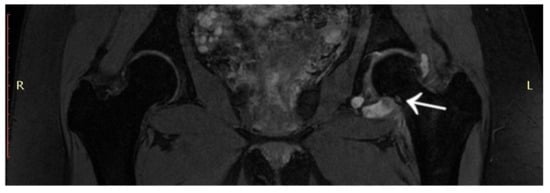

3.1. Case 1: OO Masking as Femoroacetabular Impingement (FAI)

3.6. Case 6: OO Masking as Chronic Hip Arthritis

4.3. Presentation of Osteoid Osteoma Localised Intraarticularly